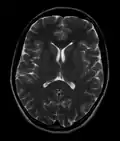

Normal axial T2-weighted MR image of the brain -

- T2-weighted (T2W) images: CSF is light, but fat (and thus white matter) is darker than with T1. T2-weighted images are useful for visualizing pathology.[26]